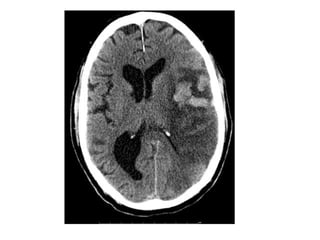

NECT showing the delta sign at the level of the torcula (dark arrows) and

hemorrhagic infarctions on the parasagittal frontal lobes (light arrows) in

a case of SSS thrombosis